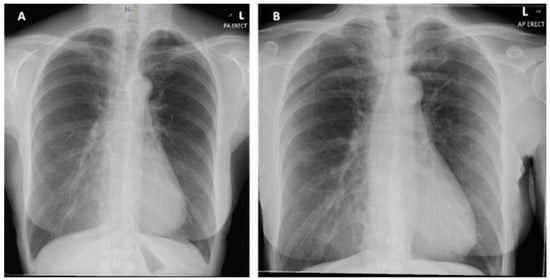

Figure 2.

(A) Posterior-anterior erect X-ray taken on initial admission in November 2019. Normal cardiothoracic ratio, normal heart size and lungs are clear with no focal abnormality. (B) PA erect X-ray taken on second admission in January 2020. No new features compared to previous X-ray.